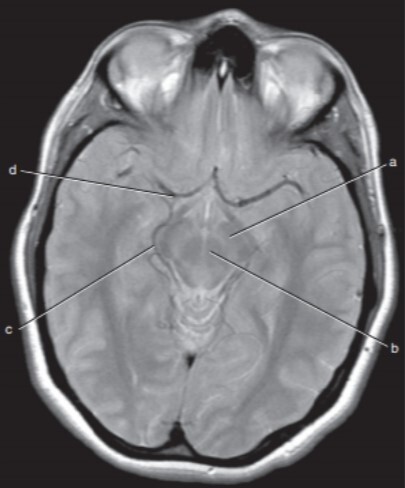

Label a,c,d

A

a=Left cerebral peduncle (of Midbrain)

c=Right ambient cistern (with Rt posterior cerebral artery)

d=Right middle cerebral artery